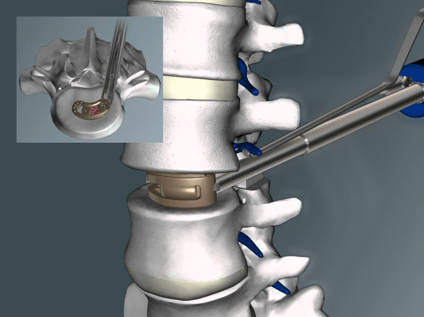

Fusiones vertebrales 360º (PLIF Y TLIF): Se denominan fusiones 360º porque además de intentar que se fusionen las articulaciones facetarias también intentamos que se fusionen los cuerpos vertebrales. Para ello tenemos que quitar el disco lumbar e introducir una caja entre los cuerpos vertebrales que rellenamos de injerto. La ventaja de las fusiones 360º es que aumentamos el porcentaje de éxito de la cirugía ya que la caja intersomática aumenta el área de fusión y da más estabilidad al montaje.

En este tipo de fusiones se intenta realizar una fusión a través de los cuerpos vertebrales. Accedemos al disco lumbar a través de incisiones abdominales. Son vías de abordaje más anatómicas lo que implica menos dolor y una recuperación más temprana. Sin embargo aunque si que consiguen muy buenas tasas de fusión, no permiten hacer unas descompresiones nerviosas tan amplias como las vías posteriores.

ALIF: El ALIF es la vía de abordaje más anterior. Únicamente sirve para acceder a los discos L4-L5 L5-S1. Permite poner cajas intersomaticas de gran tamaño y recuperar la lordosis lumbar. El mayor riesgo es lesionar la artería ilíaca, y la eyaculación retrograda si se dañan los nervios vegetativos.

XLIF: Este tipo de fusión se realiza a través de un acceso completamente lateral. Para ello hay que atravesar el músculo psoas. Permite acceder a todos los discos lumbares excepto L5-S1 y en ocasiones L4-L5 ya que las palas iliacas pueden impedirnos el acceso. Es una vía de abordaje poco agresiva cómo el ALIF y no tiene el riesgo de lesión de los vasos o el peritoneo. En cambio tiene más riesgo de lesión del plexo lumbosacro (los nervios que hacen que la pierna funcione) debido a que este atraviesa el psoas.